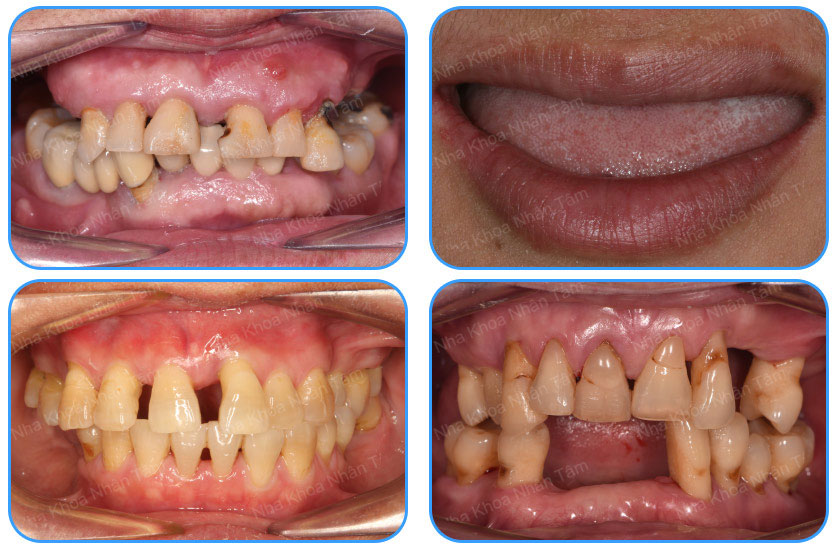

- Khách hàng bị mất răng toàn hàm, tiêu xương vùng răng trong.

- Khách hàng có răng bị sâu, hoặc viêm nha chu không thể giữ được.

- Khách hàng vừa mới nhổ răng toàn hàm, mong muốn có hàm răng cứng chắc và lâu bền.

Các trường hợp nên tiến hành trồng răng Implant All on 4